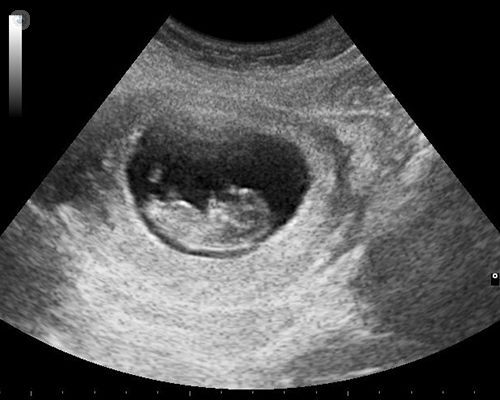

Een vitaliteitsecho is een echo die plaatsvindt rond week 7 van de zwangerschap. Het is de eerste echo die je kan doen als je zwanger bent. Het voornaamste doel van een vitaliteitsecho is om te kijken of er een levend vruchtje in je baarmoeder zit. Daarnaast kijkt de echoscopist naar een aantal andere dingen.

Deze echo kost € 40,-